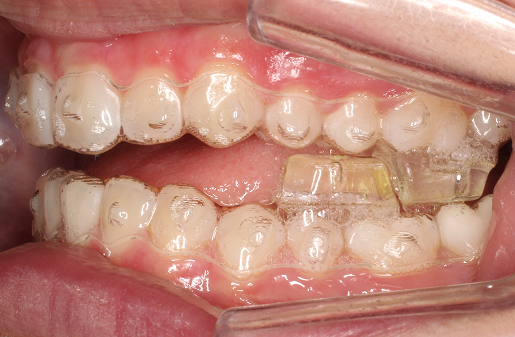

Los aligners transparentes Invisalign con bloques integrados se colocan en la superficie oclusal.

Cuando el paciente ocluye en posición adelantada, los bloques oclusales dotan al aligner del engranaje necesario para poder desplazar la mandíbula hacia delante y mantener su posición.

Se trata de un sistema que desplaza la mandíbula hacia adelante a la vez que alinea los dientes y trata la maloclusión de clase II, incluso en casos severos de mordida profunda.